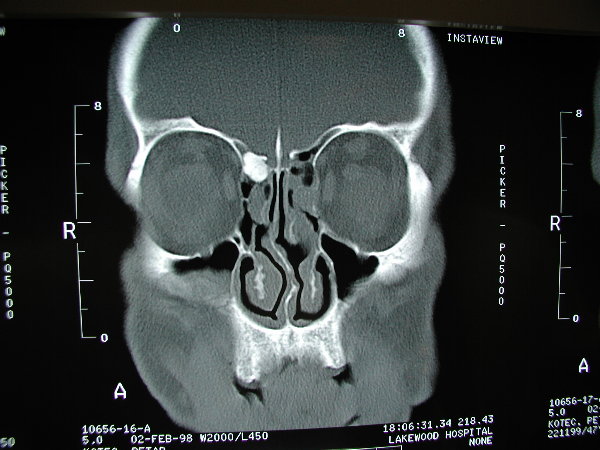

The patient above had two separate osteomas within his sinuses.  On the right it is within the frontal sinus outflow tract, and on the left it is within the frontal sinus iteslf.  The osteoma on the right was very symptomatic, causing obstruction and severe pain, while the left was asymptomatic.  The right was removed endoscopically, and the left is being observed for the time being.

An osteoma is a benign boney growth that can grow and occlude paranasal sinuses and cause problems.